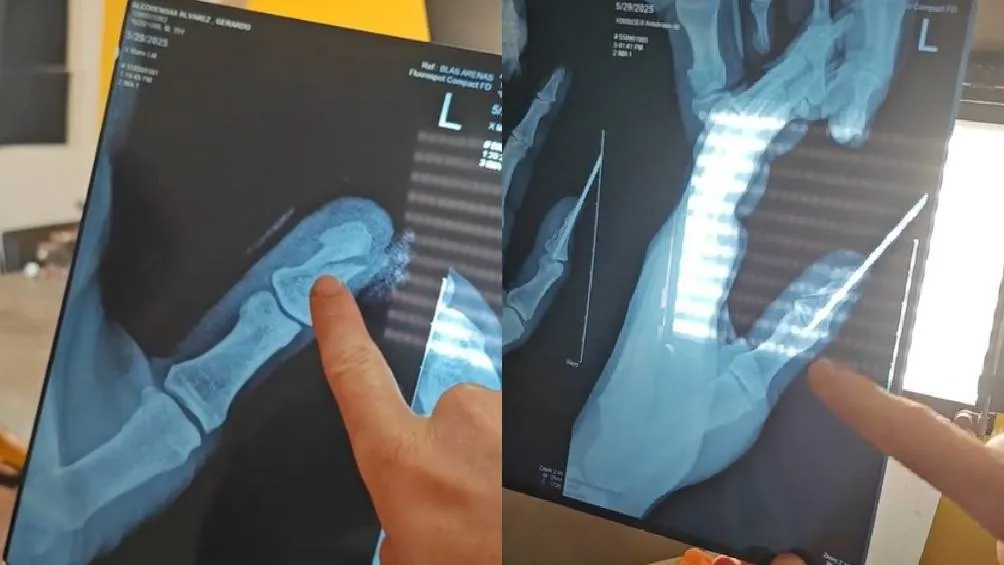

Posteriormente, en un video, el influencer explicó que las tijeras de jardinería que probó por primera vez en 2022 y que recientemente utilizó para un trabajo en su casa, le partieron el dedo “en dos”, acompañando esta explicación con radiografías en las que se puede ver qué tan lastimado resultó.

“Mi dedo va a recuperar su movilidad, le pusieron un clavito. Yo me confié y está super mal. Tengan mucho cuidado cuando usen este tipo de cosas”, comentó Jimmy, agradeciendo también todos los mensajes que recibió por parte de sus seguidores.